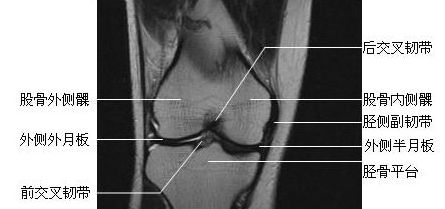

膝关节冠状面-MRI图